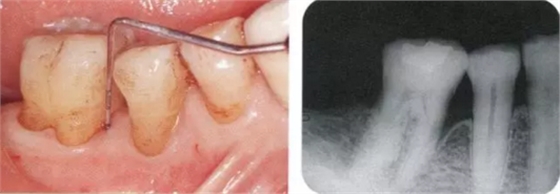

222.png

▲圖17-1,2

▲圖17-1 下頜右側(cè)磨牙區(qū)的邊緣嵴高度不齊,右下6近中有6mm的牙周袋。在這種邊緣嵴存在高低差的情況下,很容易引發(fā)食物嵌塞。

▲圖17-2 同部位的X光片。右下6近中有牙槽骨緣下牙周袋。

2222.png

▲圖18-1,2

▲圖18-1 左下5佩戴金屬冠,但是由于近遠(yuǎn)中接觸點(diǎn)的位置和大小不合適,導(dǎo)致鼓形間隙基本消失。

▲圖18-2 同部位的X光片??梢钥吹烬l下有牙結(jié)石沉積,并且有牙槽骨吸收現(xiàn)象。